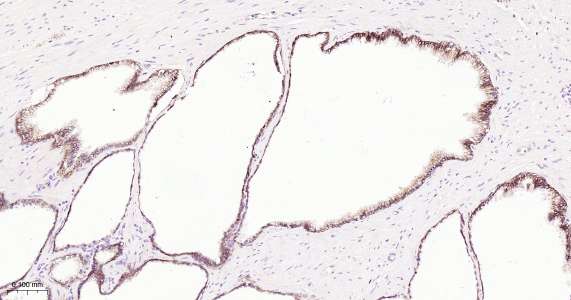

Immunohistochemical analysis of paraffin embedded human prostate cancer tissue slide using IHC0289H (Human Beta catenin IHC Kit).

Immunohistochemical analysis of paraffin embedded human colon cancer tissue slide using IHC0289H (Human Beta catenin IHC Kit).